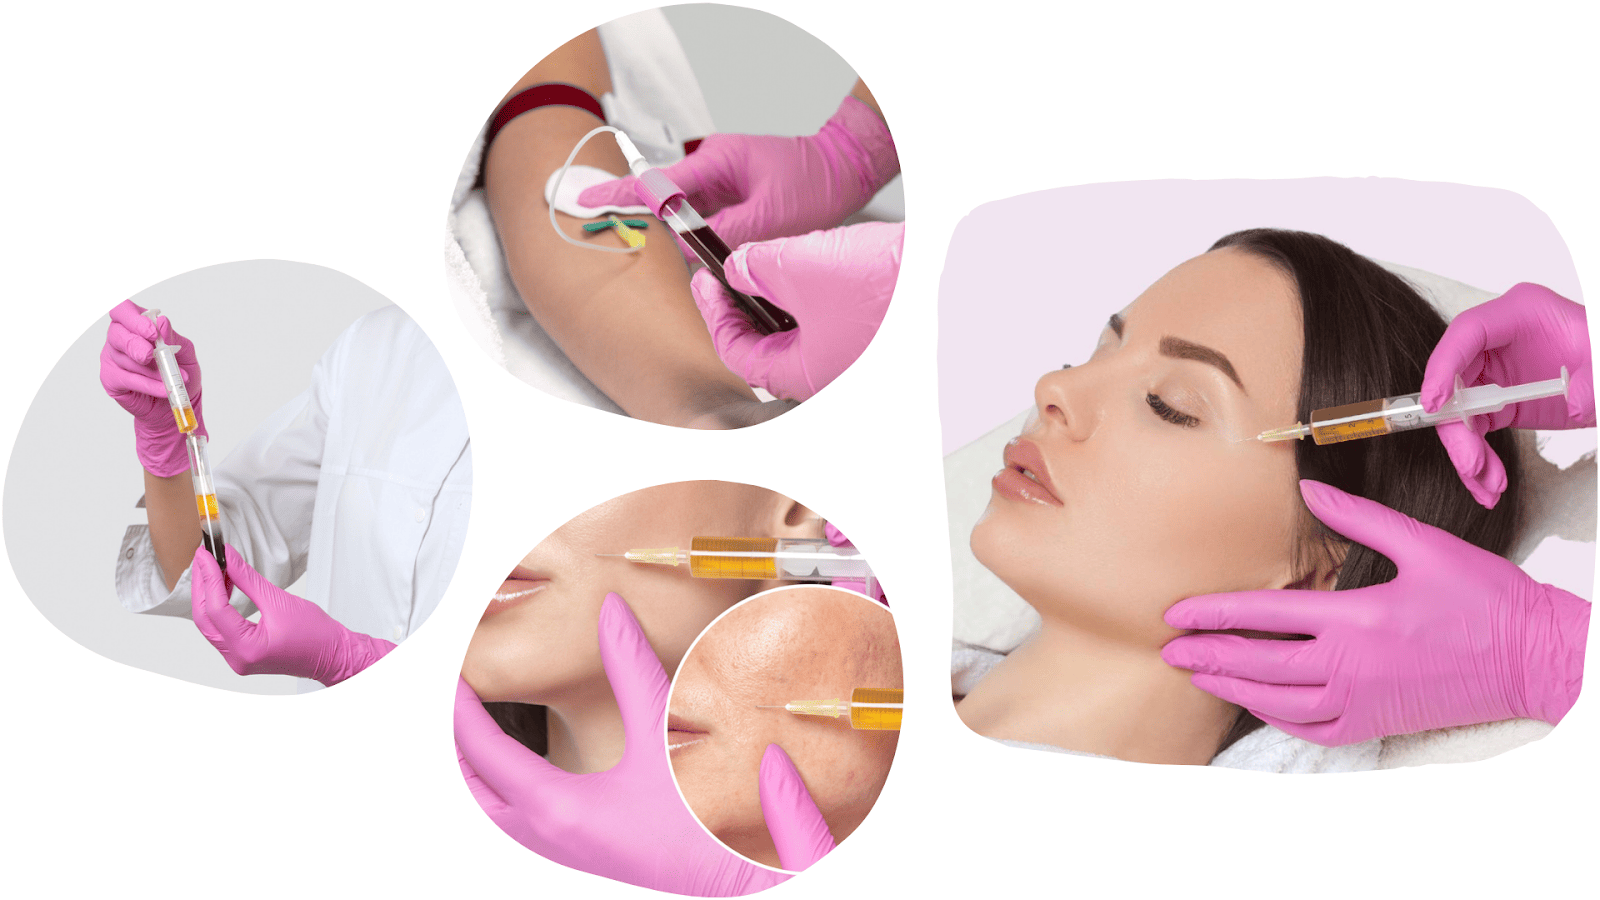

FACIAL REJUVENATION WITH PLATELET-RICH PLASMA

Facial rejuvenation with platelet-rich plasma harnesses the body’s natural power for skin regeneration and rejuvenation.

The procedure is carried out by extracting a small amount of the patient’s blood which, after processing in a high-speed centrifuge, yields platelet-rich plasma that is then applied to the skin using fine microneedles.

It is a completely natural, safe, and personalised method.

Platelets release numerous growth factors that stimulate tissue renewal, the formation of fibroblasts, collagen, and hyaluronic acid.

The result is renewed volume, reduced wrinkles, improved skin elasticity, and a more even complexion. The skin becomes hydrated, fresh, and radiant, with wrinkles becoming less pronounced and shallower.

The advantage of the treatment is that it contains no synthetic substances, there are no side effects, allergic, or immunological reactions.

The procedure is simple, painless, and completely safe, and we use it to treat the face, neck, and décolletage.

Facial rejuvenation with platelet-rich plasma is the best and most natural anti-ageing aesthetic facial treatment you can give yourself.